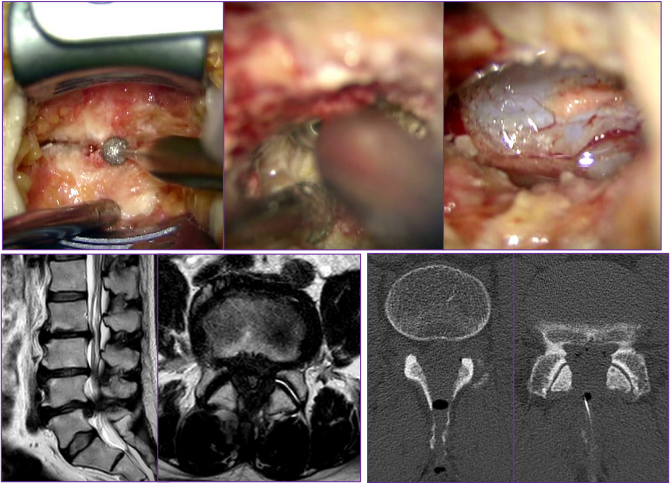

腰部脊柱管狭窄の手術方法は?

小さな皮膚切開(1椎間であれば2.5cm程)で、椎弓と呼ばれる骨の一部を削り、厚くなった靭帯や飛び出した椎間板を取り除きます。手術は、手術顕微鏡を使って行います。

椎骨と椎骨の骨のズレが脊柱管狭窄症の原因となっている場合は、固定術の併用が必要になります。